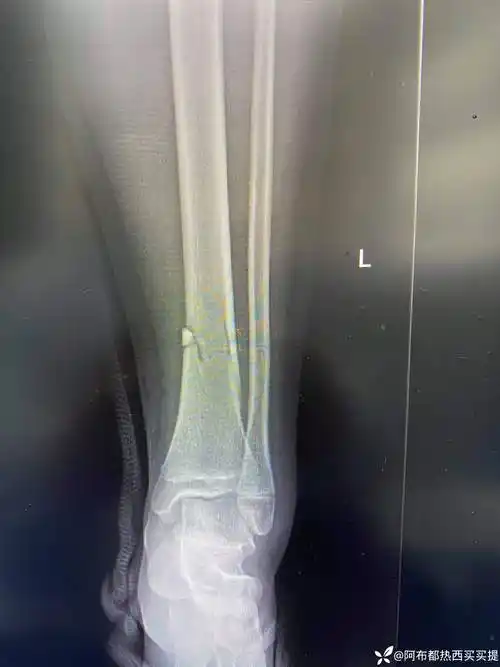

55岁男性车祸致左腓骨近端骨折 左胫骨远端粉碎性骨折,内侧开 - 抖音

一例胫骨近段粉碎骨折的完整病历